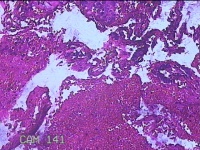

宫颈管内组织

性别

女

年龄

46岁

临床诊断

异常子宫出血

一般病史

阴道流血伴血块6天。

标本名称

大体所见

灰白暗红色不规则碎组织1.5x1.3x0.3cm一堆。

图1